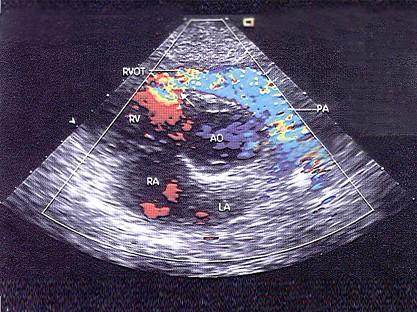

该病例最可能的诊断?(?)A.右室流出道狭窄B.肺动脉瓣狭窄C.室间隔缺损D.右室双腔心E.以上都不是

问题 该病例最可能的诊断?(?)

选项 A.右室流出道狭窄 B.肺动脉瓣狭窄 C.室间隔缺损 D.右室双腔心 E.以上都不是

答案 D